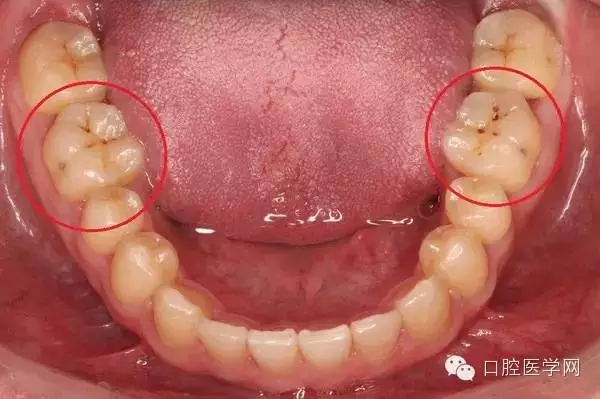

有人會發(fā)現(xiàn),自己的牙齒表面突然出現(xiàn)一點(diǎn)黑點(diǎn),但是也不覺得疼,是什么原因?qū)е卵例X變黑?如果牙齒出現(xiàn)黑點(diǎn)且不痛有兩種可能性。

一旦確認(rèn)牙齒上的小黑點(diǎn)是齲齒就應(yīng)該盡早修補(bǔ),以阻止病變的發(fā)展。如果任由其繼續(xù)發(fā)展就會變成明顯的齲洞,這時患者會對冷熱酸甜等食物刺激敏感;當(dāng)損傷進(jìn)一步到達(dá)牙髓(即老百姓說的“牙神經(jīng)”),就會疼痛難忍,嚴(yán)重影響日常生活。臨床上見到很多人都會等到牙痛得受不了,才到醫(yī)院就診。這時通常不能靠單純補(bǔ)牙來解決問題,可能還要做根管治療甚至拔除患牙、進(jìn)行假牙修復(fù),費(fèi)時費(fèi)力又費(fèi)錢,人還遭罪,可謂“小洞不補(bǔ),大洞吃苦”。